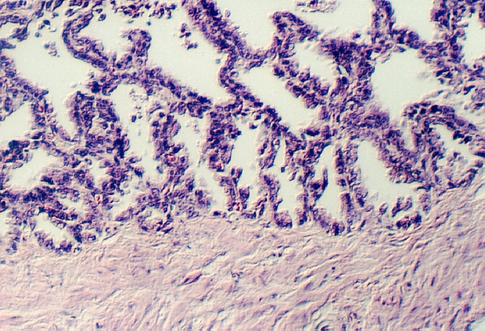

The Prostate epithelium looks cuboidal or pseudostratified low columnar in spots. Inside the glandular lumena you may see laminated bodies known as concretions. These are evident in the following photograph and help identify the organ as the prostate.

In the connective tissue there are bundles of smooth muscle which stand out

because of their homogeneous cytoplasm. Find smooth muscle in the above photograph

or the one below. What components of semen are contributed by the prostate?